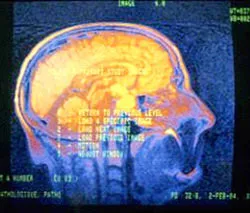

Lúc đầu, các nhà khoa học tìm cách chứng minh mối tương quan giữa thuận tay trái và chứng loạn đọc (dyslexie). Sau khi nghiên cứu những nhóm gien của hàng trăm gia đình, họ nhận ra phần lớn người thuận tay trái có gien LRRTM1. Gien này tác động đến tính không đối xứng của bộ não. Những phần bên phải và bên trái của não người (ảnh) giữ những vai trò khác nhau. Ở người thuận tay phải, bán cầu não trái điều khiển khả năng sử dụng ngôn ngữ và phát âm, trong khi bán cầu não phải điều khiển cảm xúc. Ở phần lớn người thuận tay trái, vai trò của 2 bán cầu não ngược lại. Sự thay đổi trong phân chia vùng não cho những nhiệm vụ khác nhau được thực hiện ở giữa não bởi gien LRRTM1, và sự thay đổi này dẫn đến việc sử dụng tay này nhiều hơn tay kia.